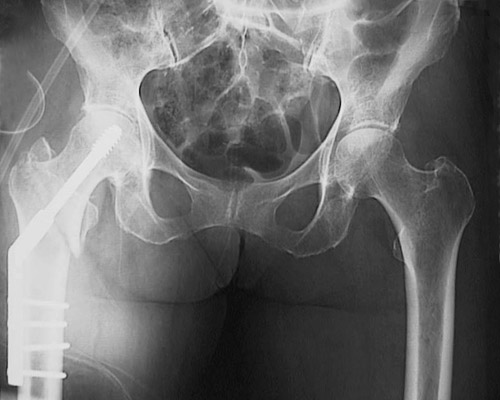

The radiograph of the pelvic region is shown above, with an intertrochanteric fracture located in the right femur of an elderly woman with osteoporosis. Below is the postoperative radiograph following surgical repair.